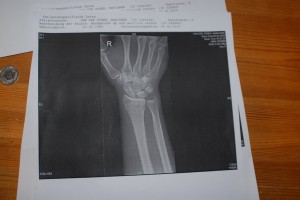

This Monday I had to get to the hospital again. New X-Rays and a good look at my arm. In Thun (CH) they wanted to operate, put a plate in my arm and cut off some muscle. That sounded like my worst nightmare and the last days I kept on dreaming about that. Waking up, thinking I’d never be able to climb again.

And again, then doctor said they were concidering operation. I started to doubt my (and his) knowlegde and asked if he could discuss the situation with his colleagues. Some more waiting, X-Rays and waiting later, he decided not to operate and give me some new plaster for 4 weeks, later the 4 weeks even changed to 3 weeks.

But at least no metal in my arms, only some hard pink plaster (read: plastic) around it for 3 more weeks.